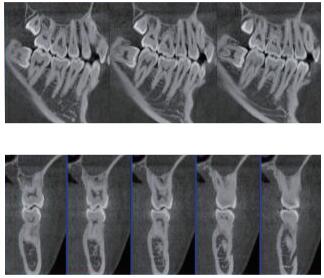

在口腔影像等細分領域,口腔CBCT的成像質量優(yōu)于CT和普放。CBCT的X線利用率更高,且生成的圖像具備很高的各項同性空間分辨率。口腔CBCT能夠針對局部斷層曲面重建生成清晰無重疊的斷層影像以及3D影像,成像效果更好,有助于醫(yī)生的診斷,對于種植、綜合診斷、正畸等牙科診斷均有較大幫助。口腔CBCT技術優(yōu)勢如下:

三維重建任意斷層

專有三維重建算法,可提供任意位置高清斷層影像。

多平面組合重建

可同時觀察軸向面、冠狀面和矢狀面圖像,方便臨床診斷。